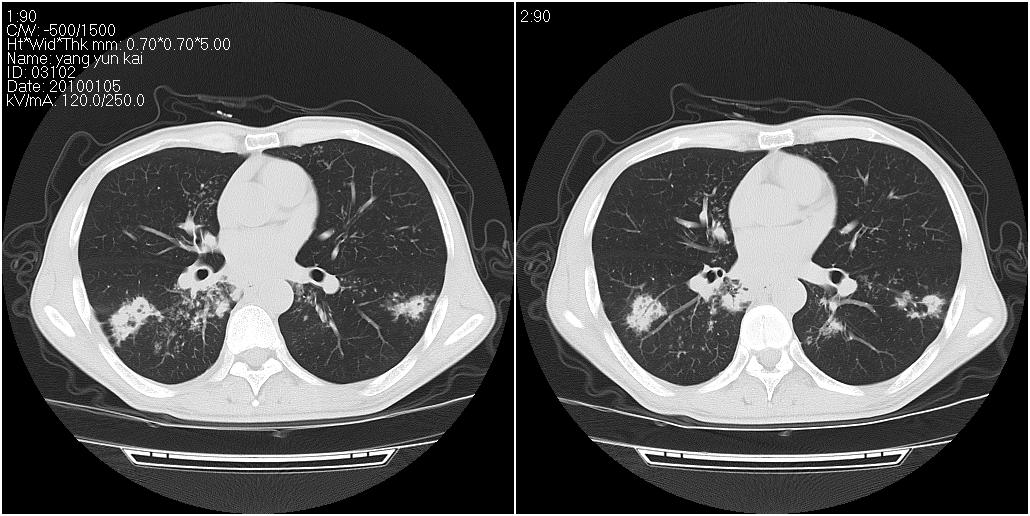

标题: CT23980:男性,47岁。近来咳痰、咳血,血沉增快(40左右),

男性,47岁。近来咳痰、咳血,血沉增快(40左右),痰中未检出结核杆菌。

符合继发性结核表现部分空洞形成并播散